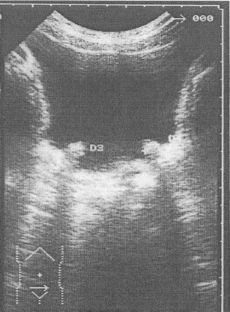

Fig. 1

Fig. 2

Fig. 3